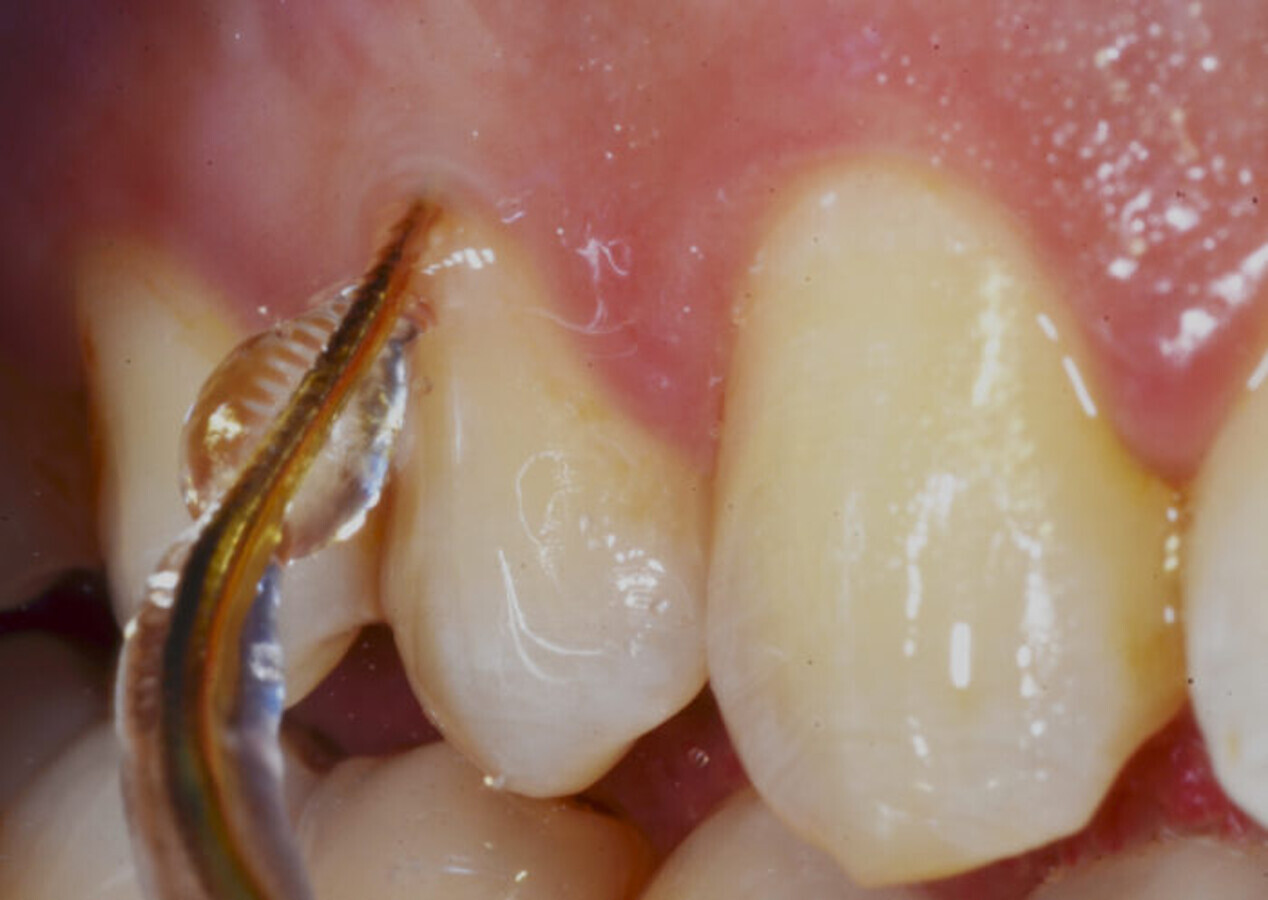

Ultrasonic instrumentation

Aerosols generated by ultrasound are an intrinsic feature of the devices.12 Therefore, in this situation of high transmissibility of the virus, it is preferable to limit the use of ultrasound in favour of manual tools. If there are biofilm and non-calcified deposits, it is also recommended to reduce the level of irrigation and power of the ultrasonic devices. In this scenario, it is highly recommended to use devices with which one can better regulate the water supply and reduce the amplitude of movement of the insert, minimising cavitation (Fig. 1). In situations where the use of ultrasound at a higher power is needed, it is important to increase the safety precautions indicated by scientific societies, such as PPE or efficient aspirators.